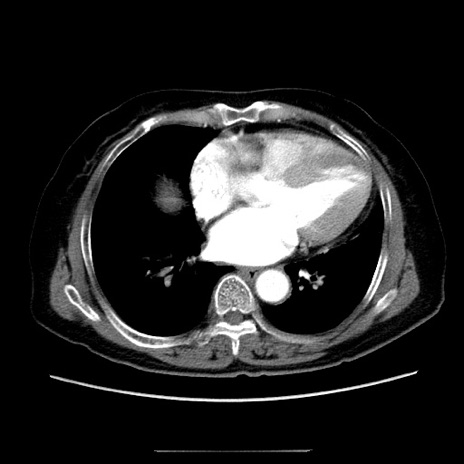

症例5(横断像)

【症例】70歳代女性

【主訴】お腹が張る

【現病歴】1週間くらい前から腹部膨満の自覚あり。昨日夜から増悪したため、本日救急外来受診。

【身体所見】意識清明、BT 36.5℃、BP 165/106mmHg、HR 80bpm、SpO2 98%、腹部:膨満、軟、自発痛・圧痛なし、触診にて不快感あり、腸蠕動音:減弱

【データ】WBC 12600、CRP 1.04